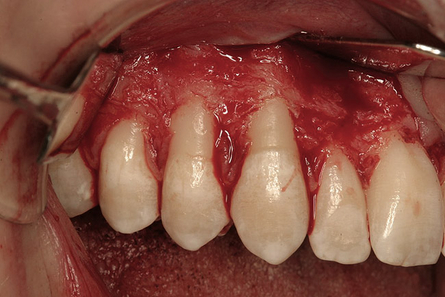

La terapia chirurgica parodontale permette una più accurata pulizia delle radici: incidendo e scollando i tessuti gengivali, l’accesso ai denti e all’osso è infatti molto più agevole. Essa permette anche di ostacolare la crescita dei batteri che vivono in assenza di ossigeno e ha il vantaggio di facilitare il controllo della placca.

L’approccio chirurgico chirurgia osseo resettiva consiste nel rimuovere il tessuto malato (la tasca) e nel ricontornare i tessuti molli (gengive) e duri (osso alveolare) rendendone uniforme l'alteza e rimuovendo picchi e irregolarità. Eliminando le anomalie del tessuto osseo e gengivale che determinano un'accumulo di placca è possibile infatti ottenere un’anatomia che permetta l’eliminazione permanente delle tasche, dei difetti ossei e di favorire le manovre di igiene domiciliare.